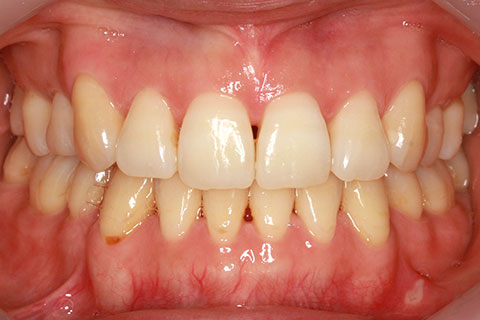

治療前

治療中

治療後

- 年齢・性別

- 42歳男性

- 治療期間

- 1年6ヶ月

- 抜歯

- なし

- 治療費

- 120万円(税込み)

- 備考

- マルチブラケットを用いた矯正治療

- 治療内容

- 反対咬合をフルリンガル矯正治療にて改善

- 施術の副作用(リスク)

- 表側矯正と比較して、歯根の角度を確立する「トルク」の力がかかりにくい。